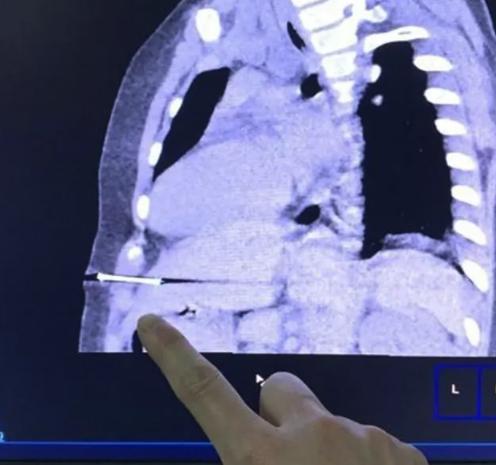

钢钉入腹距心脏仅 2.6 厘米

" 当时情况很凶险,钢钉已经刺透腹膜,扎入孩子的左侧肝脏,孩子小,片子上可以看到距离上面的心脏也仅仅 2.6 厘米,家长也非常着急,我们立即为孩子做了手术。" 董武介绍,小孩子的肝脏柔嫩脆弱,一方面肝脏异物存在时间越久就越容易引起感染,另一方面,肝脏有异物的情况下,一旦身体有肢体动作,会产生进一步损伤,可能导致腹腔出血。经过近 2 个小时的紧张手术后,一枚约 2.5 厘米长的钢钉从糖糖腹中取出。术后糖糖恢复良好,经过数日卧床休息,5 月 7 日已出院回家。